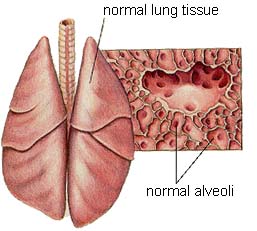

The respiratory system is responsible for taking in oxygen and eliminating waste gases like carbon dioxide. Because dogs and cats do not sweat through the skin, the respiratory system also plays an important role in regulation of temperature.

The respiratory system includes the:

- Mouth and Nose

- Trachea

- Lungs and Smaller Airways (bronchi and bronchioles)

Lungs